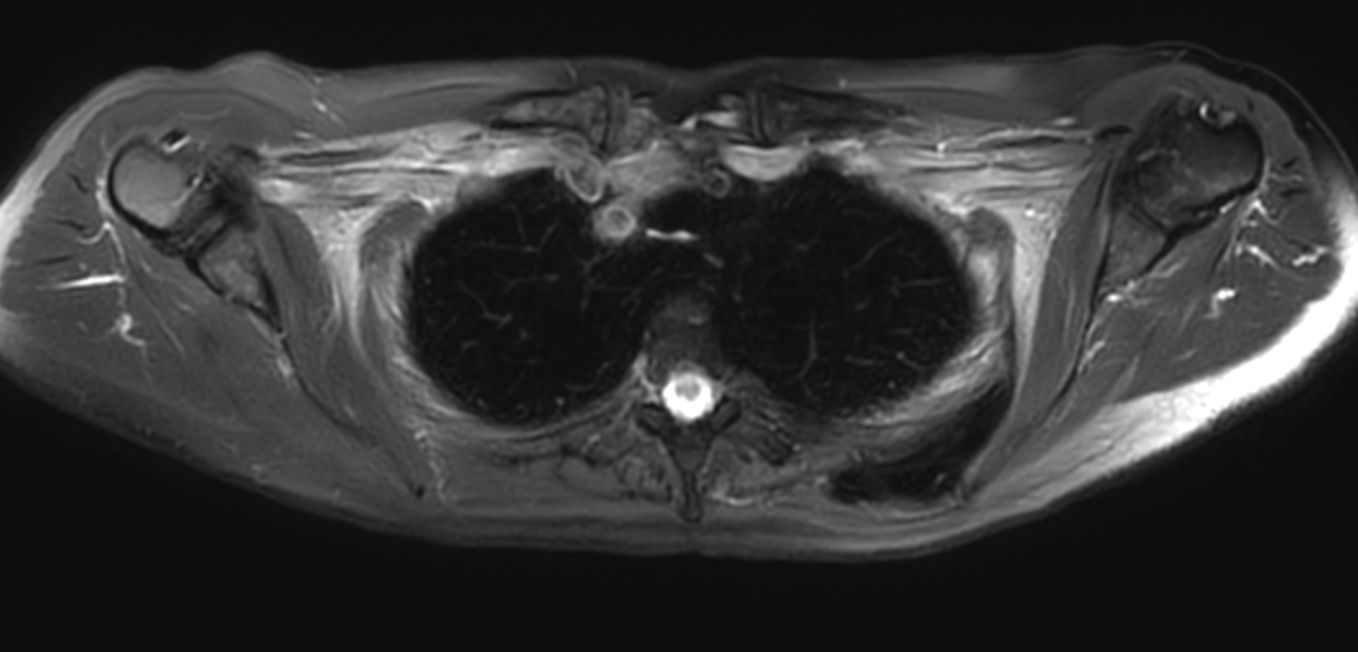

Patient with a thorax soft tissue lesion. ExamCard includes Compressed SENSE to shorten the scan time, MultiVane XD to acquire motion-free diagnostic images, 3D VANE XD helping to reduce motion artifacts during free breathing and 4D FreeBreathing to perform multi-phase contrast-enhanced MRI studies.

T2w SPIR MultiVane XD - Free Breathing